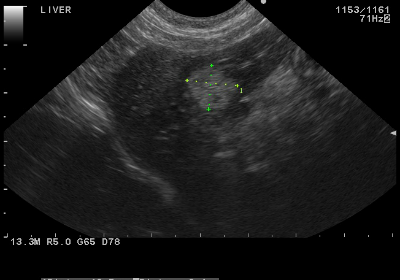

乳腺超音波検査 図1 検診評価法(文献11より. 黒い丸だけでは良悪の鑑別困難です。 ≪補足後≫ 細かいとこ見ていくので画面を正面から見てなければ、乳腺エコーの知識があっても読み取るのは難しいと思います。 結果待つしかないと思います。 良性だといいですね。. 超音波検査(エコー)による「乳がん検診」 乳腺は白 く 脂肪は灰色(くすんだ白) に映ります。そして 乳がんは黒 く映ります。 そのため、 白っぽい背景から黒いものを探す ことになります。.

第4回 肝臓がんについて ケンさん と リンちゃん のココが知りたい 疾患と検査 検査部 その他の部門 兵庫県立がんセンターについて 兵庫県立がんセンター

肝がんの診断と治療 肝がんの診断と治療 肝がんの死亡数と原因 肝がんを見つけるための定期検査 肝がんの精密検査 腫瘍生検 狙撃生検 肝がんの発生 高分化型肝がん 早い時期の肝がん 腹腔鏡での腫瘍パターン 肝がん以外 血管造影による肝がんの診断 血管